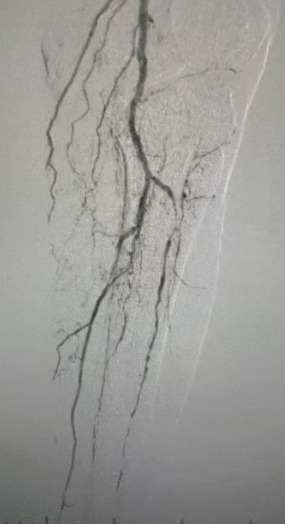

・術前イメージング: 両側下肢動脈における重度のびまん性石灰化狭窄症

複雑な血管状態を考慮して、ThorCrack末梢IVLバルーン拡張カテーテルシステムを選択しました。 患者の耐性が限られているため、両方の下肢に段階的な介入手順が実行されました。

外科的成果

処置後、動脈狭窄は大幅に改善し、血流が増加し、皮膚の温度が上昇しました。 術後の合併症は発生しませんでした。 患者と外科チームの両方が結果に非常に満足していました。